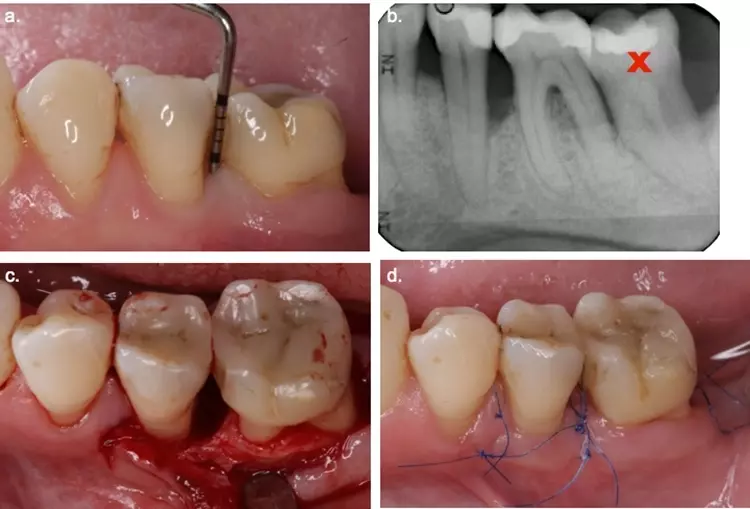

In der Unterkieferfront konnte die Mundhygiene wegen des Engstandes und der Verschachtelung nur eingeschränkt durchgeführt werden. Distal der Zähne 32 und 42 zeigten sich zudem persistierende erhöhte Sondierungswerte.

Die weitere Planung erfolgte mit der Klinik für Kieferorthopädie und Kinderzahnmedizin der Universitätszahnkliniken [5]. Es wurde entschieden, die Zähne 32 und 42 zu extrahieren und einen möglichst weitgehenden Lückschluss durch eine kieferorthopädische Therapie zu erzielen.

In einem ersten Schritt erfolgte nach Bildung eines Mukoperiostlappens die schonende Extraktion der Zähne 32 und 42. Die intraoperativ detektierten vertikalen Defekte an den Zähnen 33 und 43 wurden mit Schmelz-Matrix-Proteinen behandelt und primär chirurgisch verschlossen.

In der 6-monatigen Heilungsphase wurde ein Interimsersatz mit handgebogenen Klammern erstellt, um die Lücken in der Unterkieferfront prothetisch zu schließen. Danach erfolgte die kieferorthopädische Ausformung des Unterkieferzahnbogens mit festsitzenden Apparaturen. Die definitive ästhetische Rehabilitation erfolgte im Anschluss an diese Therapie und wurde durch kleine approximale Kompositfüllungen erreicht (Abb. 12 und 15).